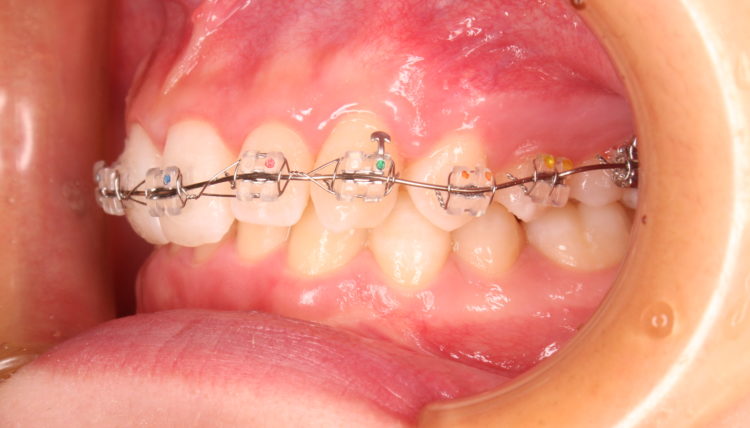

矯正装置を装着した状態です。

先ずは、上顎の歯に矯正装置(ブラケットとワイヤー)の装着です。

この段階では、下の歯に装置は付けれません。

ブラケットを装着するスペースが不足している為です。

上顎前歯をある程度圧下して(上方に押し上げて)から、下の歯に矯正装置を装着します。